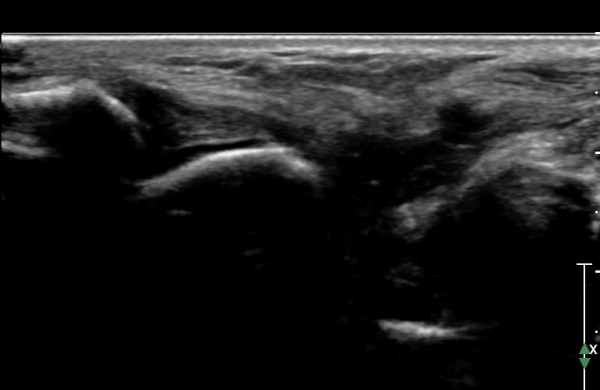

ÇϺΠ½ÅÀü ¶ì(inferior extensor retinaculum) ÀÇ frondiform Àδë Á¾´Ü¸é°Ë»ç¿¡¼­

frondiformÀÎ´ë ½ÉºÎ°¡Áö ÁÖº¯ ¼ö¾×Àú·ù°¡ °üÂûµÇ°í Á·±Ùµ¿ °æºÎÀδ밡 ³Ê¹« ¶Ñ·ÇÈ÷

°üÂûµÈ´Ù(»çÁø 5, 6, 7).